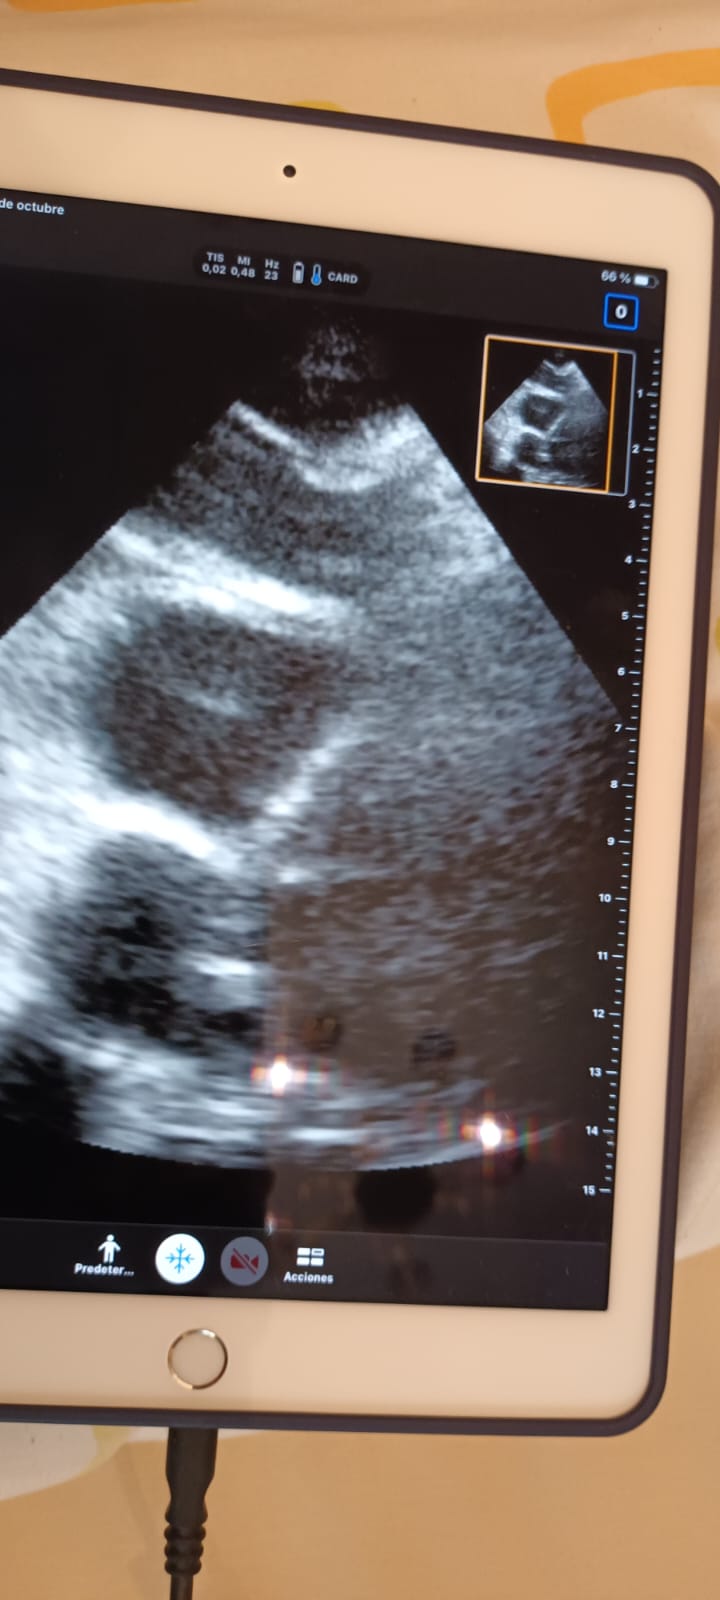

Al realizar ecografía Doppler miembro inferior derecho, objetivamos en región ilíaca, femoral, y poplítea, ocupación por material ecogénico, y que no resultan compresibles.

Realizamos también ecocardioscopia, encontrando un trombo en transición en ventrículo derecho.